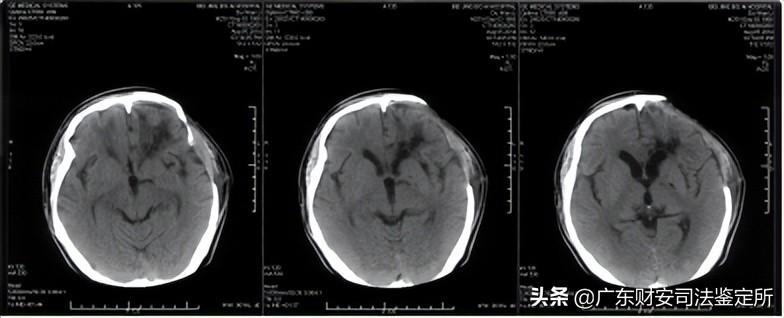

2014-6-16颅面部CT片示:双侧额骨、双眼眶壁、双侧鼻骨等颅面骨多发骨折,颅底骨折,左侧开颅术后,左侧额颞顶部分颅骨缺损,局部脑组织稍向外膨隆,颅内积气,双侧额叶可见少量高密度影,右侧额部可见金属探头,左侧额叶可见不规则大片状低密度区,左侧侧脑室稍受压,局部中线结构稍右偏。(见附件5-A)

2014-6-24颅脑CT片示:右侧额部金属探头已拔除,左侧脑室受压解除,中线结构居中,余基本同前。(见附件5-B)

2014-8-5首次术后颅脑CT片示:左侧开颅术后,额颞部分颅骨缺损,双侧额叶、左侧基底节区、侧脑室旁均可见软化灶、形态不规则,左侧侧脑室轻度扩张,中线结构居中。(见附件5-C)

2014-9-18修补术后复查颅脑CT片示:左侧额颞部颅骨减压修补术后,胼胝体、左侧基底节区可见斑片状低密度灶,双侧额叶可见不规则低密度灶,中线结构居中。(见附件5-D)